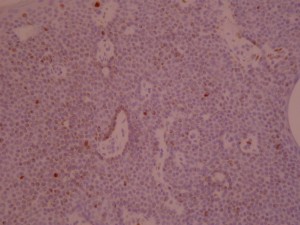

ki-67 staining of reticulo-acanthotic type of SKs.

ki-67 staining of reticulo-acanthotic type of SKs.

ki-67 staining of reticulo-acanthotic type of SKs.

ki-67 staining of reticulo-acanthotic type of SKs.